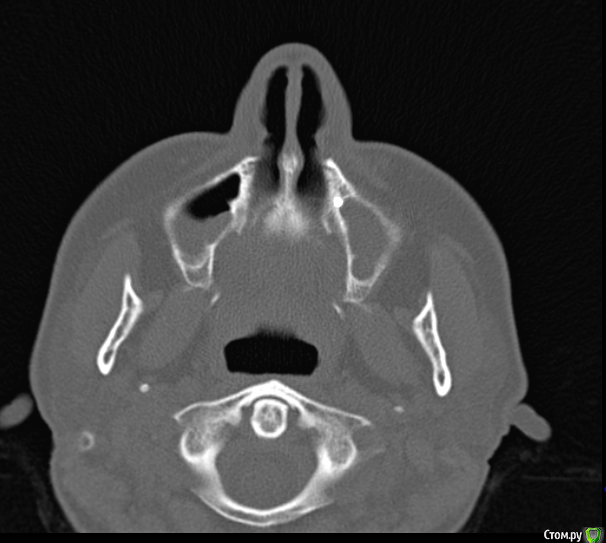

Надежда В. Опубликовано 29 августа, 2017 Поделиться Опубликовано 29 августа, 2017 (изменено) Уважаемые специалисты! Нужны ваши мнения по поводу целесообразности удаления прижившегося импланта. Он был поставлен около 2 лет назад в верхнюю челюсть. Ничего не беспокоило, а 2 недели назад начался левоосторонний гайморит. Как выяснилось, имплант торчит в гайморовой пазухе. На данный момент гайморит практически пролечен. Лор говорит, что надо проконсультироваться со стоматологами по поводу удаления импланта. Стоматологи говорят, что решение об удалении я должна принять сама. Изменено 29 августа, 2017 пользователем Надежда В. Ссылка на комментарий

Bier Опубликовано 29 августа, 2017 Поделиться Опубликовано 29 августа, 2017 у вас с другой стороны зуб - очаг инфекции. А гайморит бывает и не связанный с зубами. Более того для понимания расположения имплантата нужно посмотреть КТ, а не панорамный снимок. Ссылка на комментарий

Надежда В. Опубликовано 29 августа, 2017 Автор Поделиться Опубликовано 29 августа, 2017 С другой стороны киста уже давно. КТ добавила. у вас с другой стороны зуб - очаг инфекции. А гайморит бывает и не связанный с зубами. Более того для понимания расположения имплантата нужно посмотреть КТ, а не панорамный снимок. Ссылка на комментарий